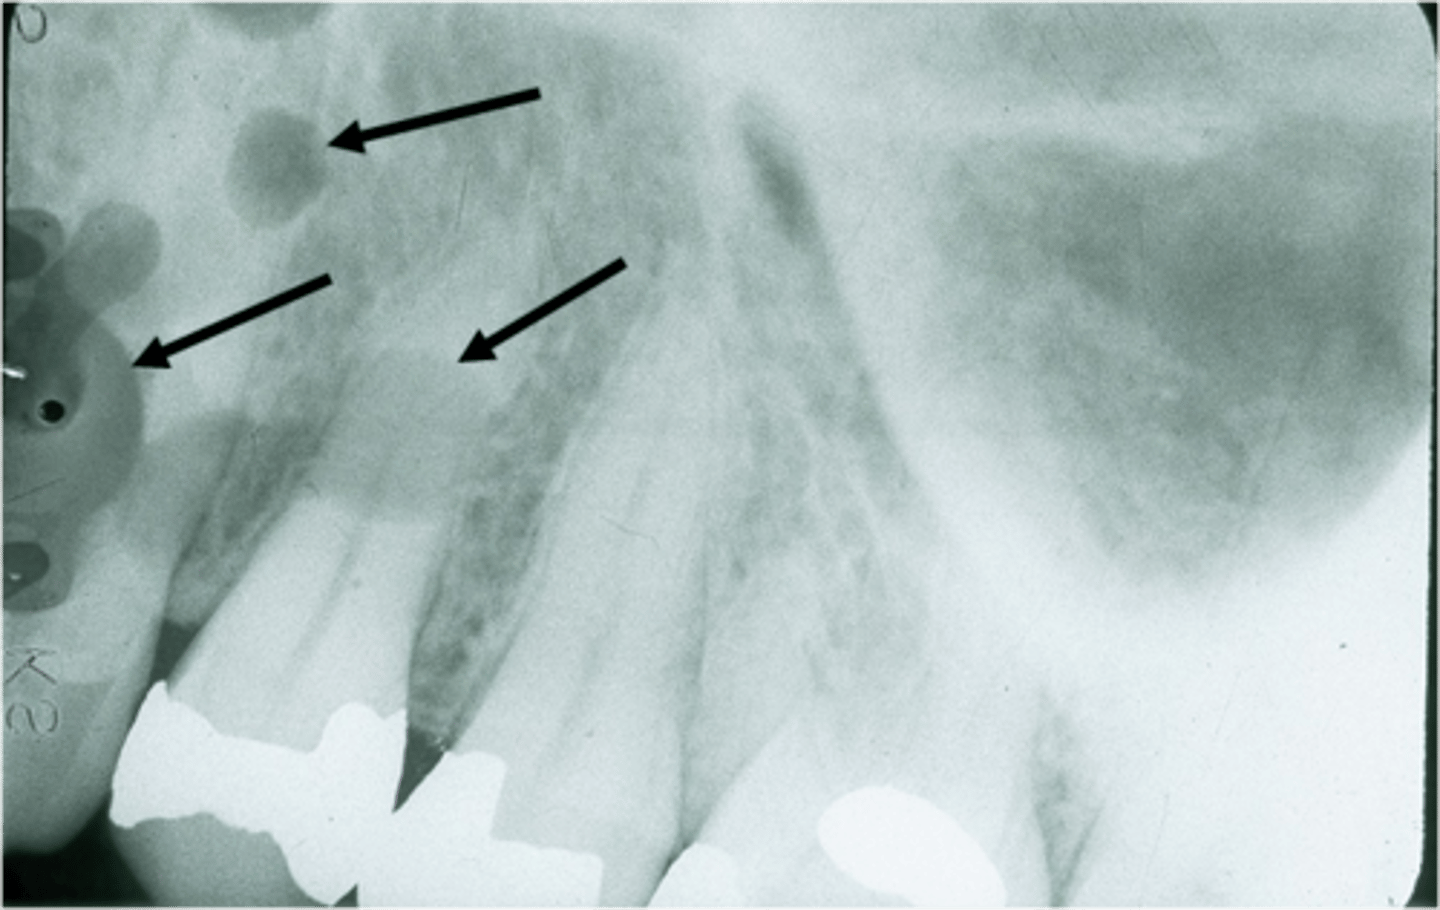

Incorrect PID postioning error can cause this

Cone cutting